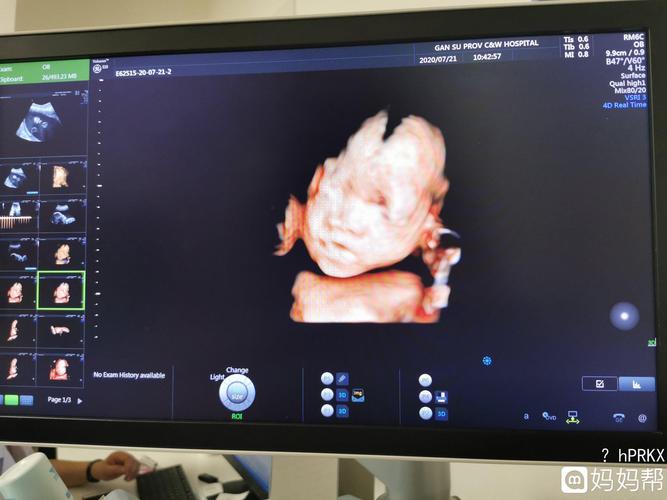

胎儿鼻骨缺失和或发育不良的医生专业指导

今天照了四维医生说鼻骨未见为娘很是担

宝宝没有鼻骨,会不会是畸形

有没有跟我一样的宝妈,胎儿鼻骨及颌骨扁平